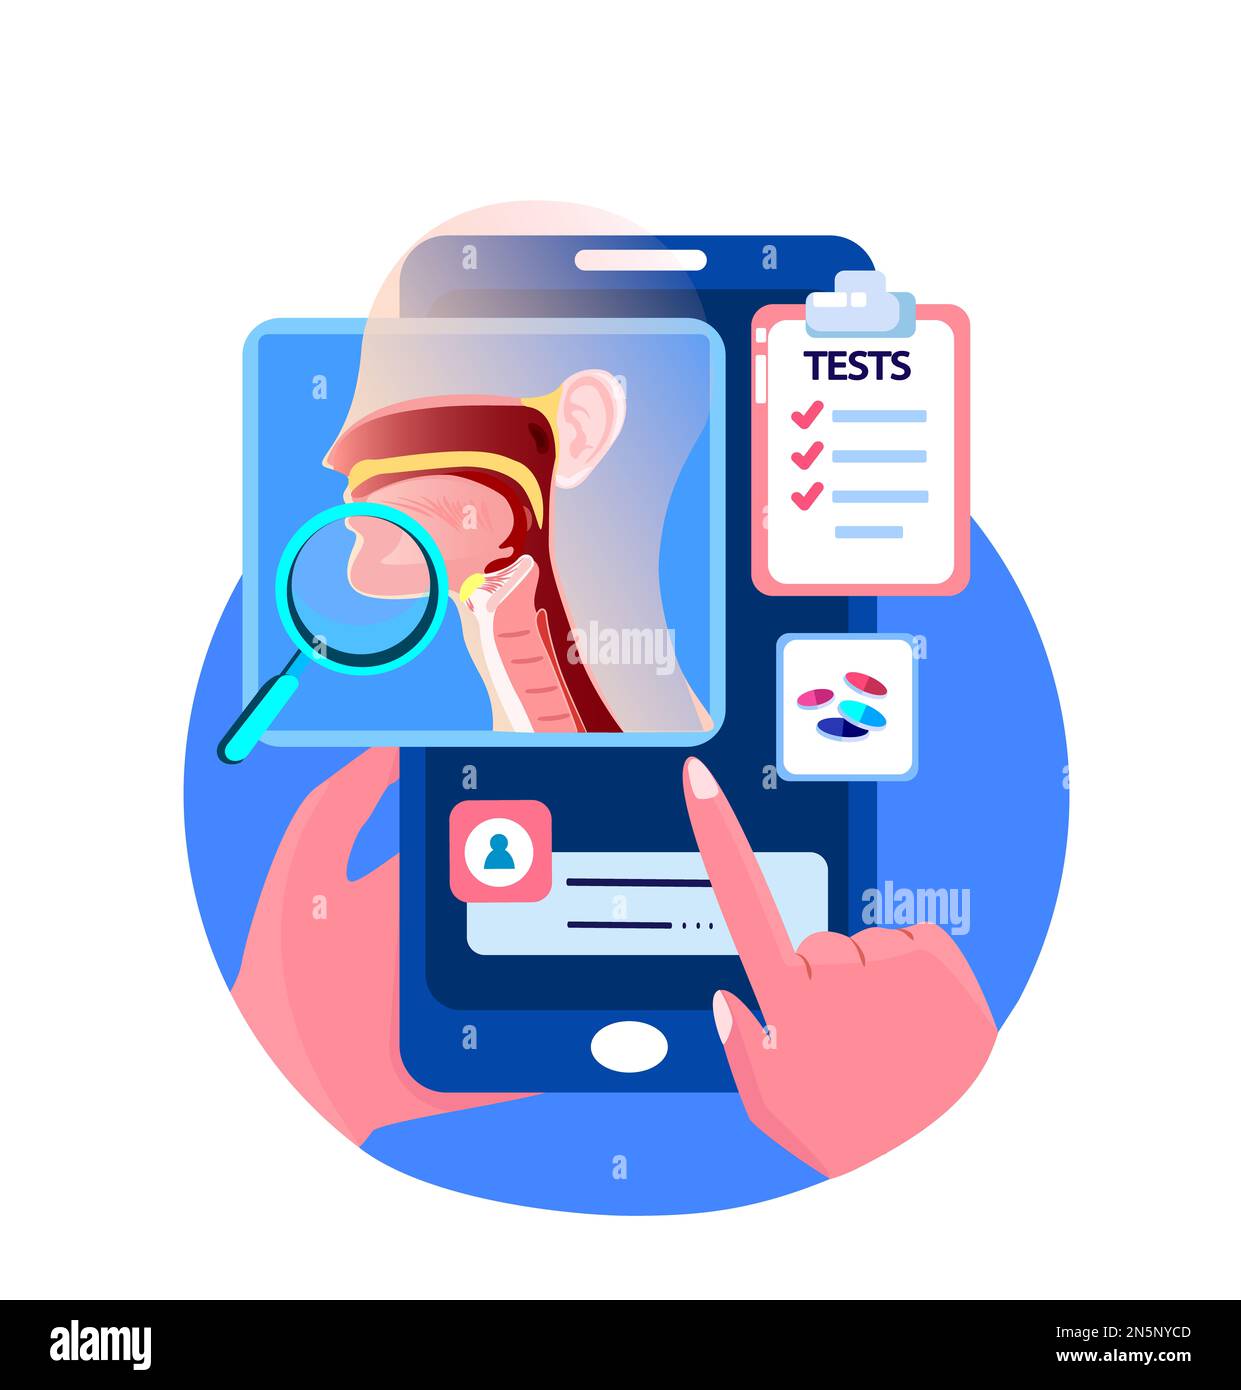

Online HNO-Doctor Consultate Patient.Inflammation,Nose,Rachen.Tonsilis,Halsschmerzen,Kehlkopf,Angina,Sinusitis Digitale Behandlung. HNO-Klinik. Internet-Hom Stockfotohttps://www.alamy.de/image-license-details/?v=1https://www.alamy.de/online-hno-doctor-consultate-patientinflammationnoserachentonsilishalsschmerzenkehlkopfanginasinusitis-digitale-behandlung-hno-klinik-internet-hom-image519866790.html

Online HNO-Doctor Consultate Patient.Inflammation,Nose,Rachen.Tonsilis,Halsschmerzen,Kehlkopf,Angina,Sinusitis Digitale Behandlung. HNO-Klinik. Internet-Hom Stockfotohttps://www.alamy.de/image-license-details/?v=1https://www.alamy.de/online-hno-doctor-consultate-patientinflammationnoserachentonsilishalsschmerzenkehlkopfanginasinusitis-digitale-behandlung-hno-klinik-internet-hom-image519866790.htmlRF2N5NYB2–Online HNO-Doctor Consultate Patient.Inflammation,Nose,Rachen.Tonsilis,Halsschmerzen,Kehlkopf,Angina,Sinusitis Digitale Behandlung. HNO-Klinik. Internet-Hom

Online ENT-Diagnostic Inflammation.Touchscreen Mobile Anwendung.Smartphone Nase,Rachen Beratung. Tonsilis, Kehlkopf, Sinusitis Digitale Behandlung Stockfotohttps://www.alamy.de/image-license-details/?v=1https://www.alamy.de/online-ent-diagnostic-inflammationtouchscreen-mobile-anwendungsmartphone-naserachen-beratung-tonsilis-kehlkopf-sinusitis-digitale-behandlung-image519866829.html

Online ENT-Diagnostic Inflammation.Touchscreen Mobile Anwendung.Smartphone Nase,Rachen Beratung. Tonsilis, Kehlkopf, Sinusitis Digitale Behandlung Stockfotohttps://www.alamy.de/image-license-details/?v=1https://www.alamy.de/online-ent-diagnostic-inflammationtouchscreen-mobile-anwendungsmartphone-naserachen-beratung-tonsilis-kehlkopf-sinusitis-digitale-behandlung-image519866829.htmlRF2N5NYCD–Online ENT-Diagnostic Inflammation.Touchscreen Mobile Anwendung.Smartphone Nase,Rachen Beratung. Tonsilis, Kehlkopf, Sinusitis Digitale Behandlung

Online-HNO-Arztberatung Patient. Entzündung Nase, Rachen. Tonsilis, Halsschmerzen, Kehlkopf, Sinusitis Digitale Behandlung. Internet-ORL-Klinik. Internet Stockfotohttps://www.alamy.de/image-license-details/?v=1https://www.alamy.de/online-hno-arztberatung-patient-entzundung-nase-rachen-tonsilis-halsschmerzen-kehlkopf-sinusitis-digitale-behandlung-internet-orl-klinik-internet-image519866789.html

Online-HNO-Arztberatung Patient. Entzündung Nase, Rachen. Tonsilis, Halsschmerzen, Kehlkopf, Sinusitis Digitale Behandlung. Internet-ORL-Klinik. Internet Stockfotohttps://www.alamy.de/image-license-details/?v=1https://www.alamy.de/online-hno-arztberatung-patient-entzundung-nase-rachen-tonsilis-halsschmerzen-kehlkopf-sinusitis-digitale-behandlung-internet-orl-klinik-internet-image519866789.htmlRF2N5NYB1–Online-HNO-Arztberatung Patient. Entzündung Nase, Rachen. Tonsilis, Halsschmerzen, Kehlkopf, Sinusitis Digitale Behandlung. Internet-ORL-Klinik. Internet